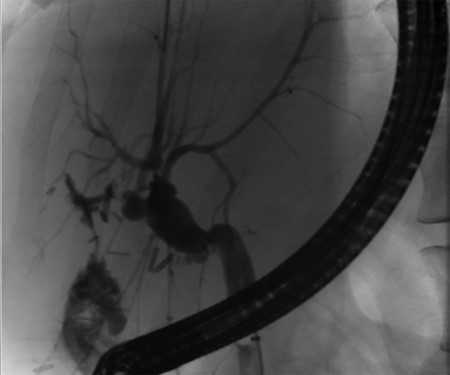

Post-operative ERCP displaying left sided intrahepatic duct biliary dilatation.

A 35-year-old female with a medical history significant for acute biliary pancreatitis status post laparoscopic cholecystectomy, presented to the surgery clinic as a new consult for a large cystic liver mass with increasing abdominal pain for 2 weeks. Patient reported suffering from severe pain in right chest, shoulder and diffuse abdominally that worsened with standing. Patient complained of inability to inspire due to pain and a 10-pound weight gain over 2 months. She confirmed decreased appetite especially with solids, nausea and emesis, alternating constipation and diarrhea, bruising, and pruritus at night. Computed tomography (CT) scan demonstrated a peripherally septated 10 x 7 cm cystic mass in the liver with intrahepatic biliary dilation (Fig. 1). The patient was referred for endoscopic retrograde cholangiopancreatography (ERCP) to establish preoperative biliary anatomy and was found to have moderate compression of the common hepatic duct managed with a right hepatic biliary endoprosthesis (Fig. 2); no obvious communication of the biliary tree with the cystic lesion was seen. Patient symptoms persisted despite optimizing with a protein-rich liquid diet; thus, the decision was made to proceed with the surgical plan for an open partial central hepatectomy. The patient was taken to the operative theater. After induction of general anesthetic, an upper midline incision was made. Inspection of the abdomen and liver showed no metastatic lesions grossly or with ultrasonographic imaging. The cyst was visible upon entry into the abdomen with no solid component to the mass in proximity to the cystic neoplasm. The second portion of the duodenum was adherent to the cyst with inflammatory adhesions and was quite boggy. A partial central hepatectomy was performed; a 3 mm biliary duct was found communicating to the cyst only with no drainage to the minimal liver parenchyma that was removed (Fig. 3). The cyst was resected en-bloc and was sent for permanent section (Fig. 4), which diagnosed the tumor as a low-grade mucinous cystic neoplasm measuring 8.5 × 7.2 × 6.4 cm. Microscopy revealed a smooth-walled, multiloculated cyst filled with a yellow-golden, semi-transparent and mucinous fluid (Fig. 5a–c). The cyst was lined by a mucinous epithelium with ovarian-type stroma. No high-grade dysplasia or malignancy was identified. The postoperative course was uneventful, and the patient was discharged on postoperative day 6. At the 4-week postoperative visit, the patient was healing well with some incisional soreness; patient was seen for removal of her biliary endoprosthesis, and ERCP found left sided intrahepatic duct biliary dilatation including a small biliary fistula from the left system (Fig. 6) with the appearance of torque on the extrahepatic biliary tree. A biliary endoprosthesis was left in place, and the patient returned for repeat ERCP 4 weeks later with resolution of all findings (Fig. 7). At present, patient remains alive with no signs of recurrence.